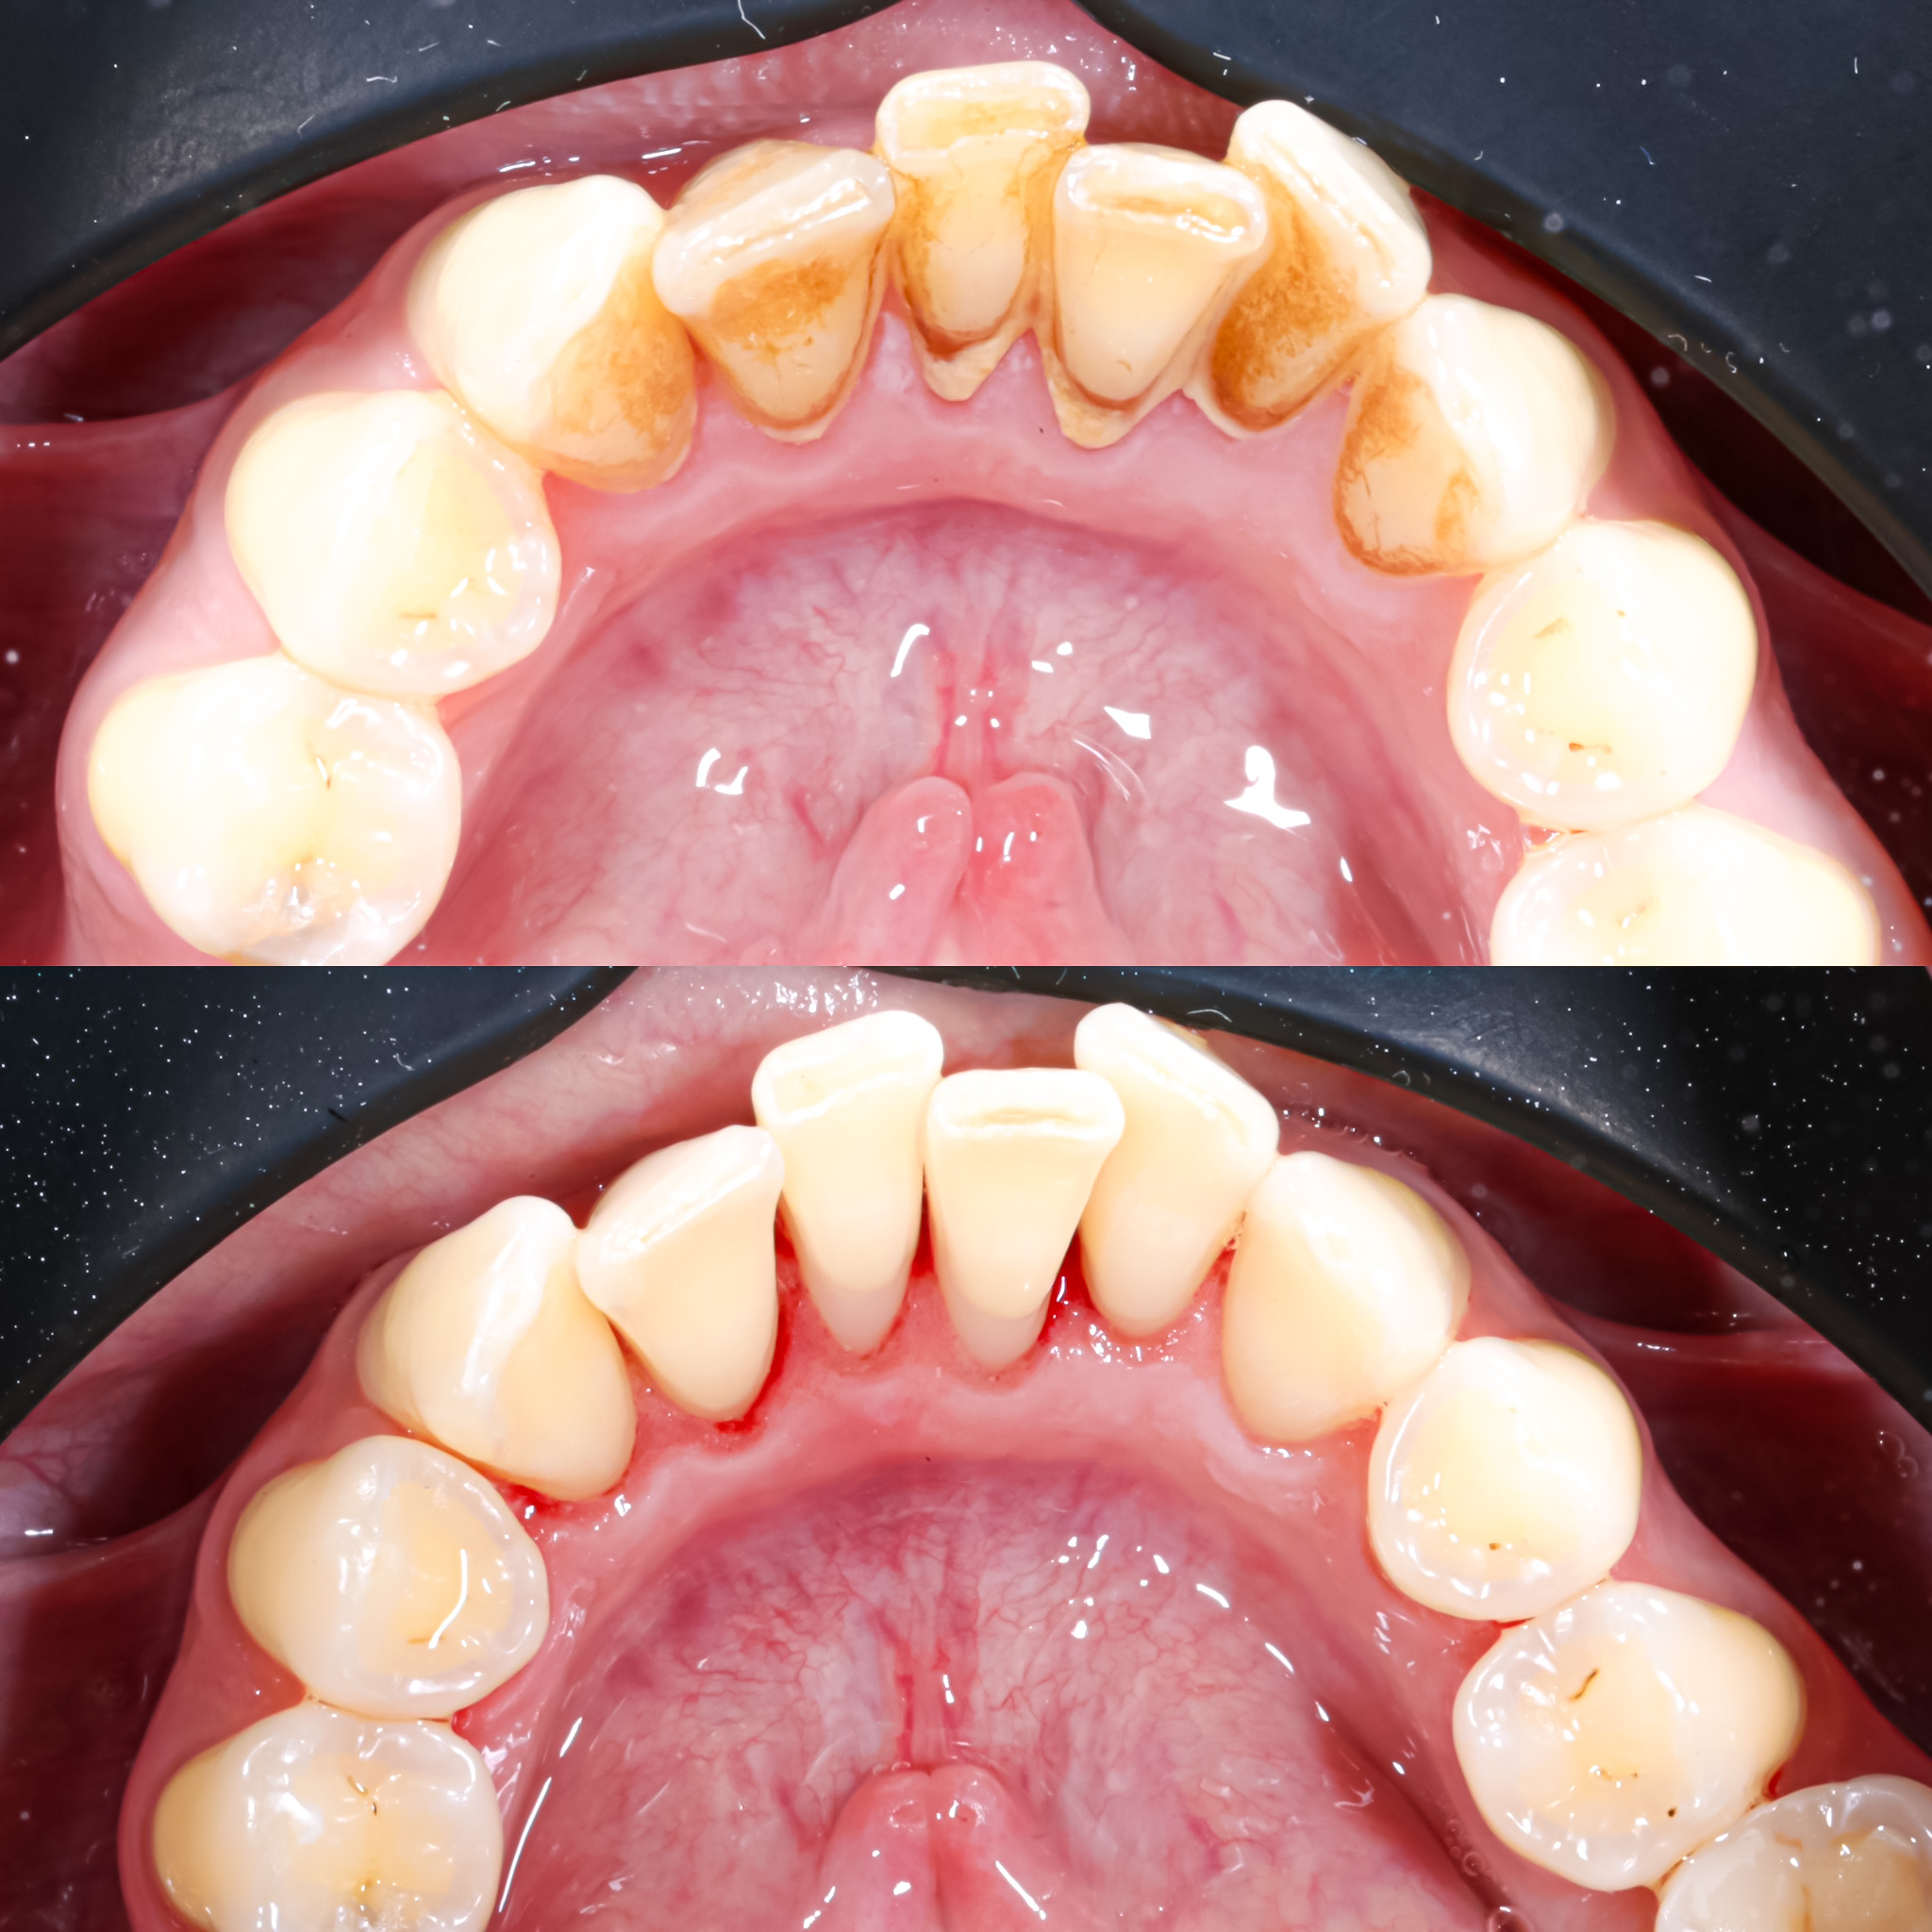

Галерея

Професійна гігієна (чистка) зубів складається з кількох етапів

Ультразвукова чистка зубів

Зубний камінь, в залежності від місця утворення, поділяється на над- та підясенний. Найбільшу небезпеку для здоров'я зубів становить другий тип, адже це дуже сприятливе середовище для шкідливих бактерій.

При проведенні професійної гігієни застосувується ультразвуковий скалер, що дозволяе видалити зубний камінь разом з хвороботворними бактеріями з підясенних кишень.

Повітряно-абразивна чистка зубів (Air Flow)

Завдяки піскоструменевому апарату з технологією Air Flow, який використовуючи тиск повітря та води, подає на зубну емаль спеціальний абразивний склад, зуби можна очистити не лише від м’якого нальоту, а й від пігменту. Для видалення нальоту, в Космічній стоматології Драганчука ми використовуємо KaVo prophy pearls supragingival calcium carbonateneutral.

Чистка зубів щіточками та пастами

Фінальний етап професійної гігієни - полірування спеціальними щіточками та пастою, щоб усунути мікротріщини та шорохуватості, що виникли після чистки та видалити залишки нальоту, що могли в них залишитись. Це дозволяє суттєво уповільнити формування нових відкладень.